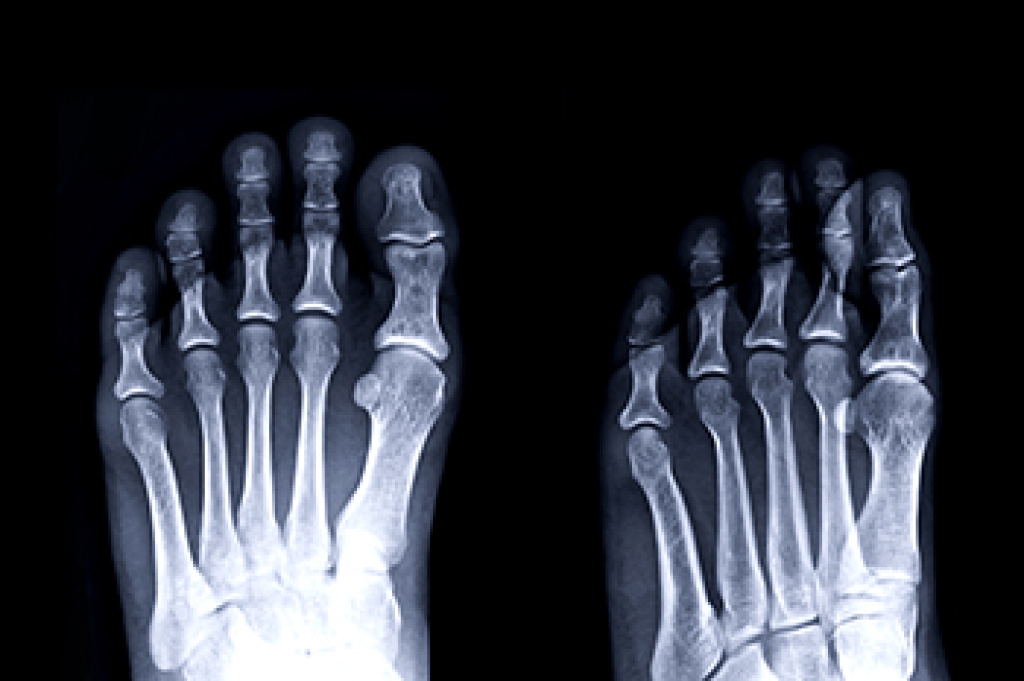

In many cases the cause of toe pain is obvious, but in others, a podiatrist may want to use more advanced methods to determine the problem. These can range from simple visual inspections and sensation tests to X-rays and MRI scans. Prior medical history, family medical history, and any recent physical traumatic events will all be taken into consideration for a proper diagnosis.